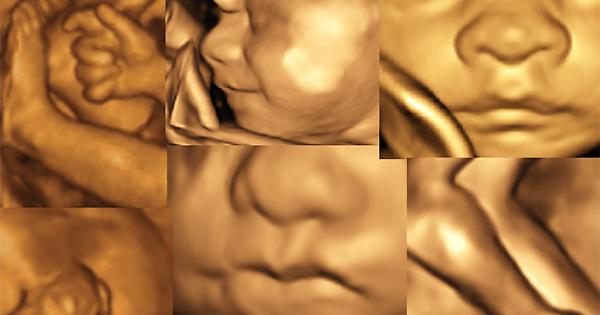

Sempre più spesso, i servizi erogati per la tutela del benessere e della salute della Donna e del Bambino rappresentano un indicatore di qualità dell’intera offerta sanitaria erogata alla comunità. Nell’ottica di tale “concezione moderna di salute”, la medicina materno-fetale non può non ricoprire un ruolo prioritario, essendo l’unico momento della vita di una donna in cui “è possibile definire il benessere del paziente presente (mamma) e del paziente futuro (feto)”. Per molteplici aspetti socio-economici, la maternità ha subito negli ultimi anni notevoli cambiamenti, in primis fra tutti l’essersi spostata come evento nella “medio-tarda” età fertile. Tale tendenza, che non potrà che continuare, induce nella coppia la pianificazione di un numero sempre inferiore di figli, spesso ricorrendo a tecniche di procreazione medicalmente assistita (e quando necessario anche con utilizzo di gameti eterologhi), aumenta potenzialmente i rischi materni e fetali (gravidanza a rischio), ma al contempo incrementa esponenzialmente il desiderio/necessità di predizione di benessere. Ecco che diventa “normale” la richiesta della coppia del “massimo” in termini di aspettativa di salute, di predizione del rischio e di diagnosi rapide, veloci, esaustive ed accurate. Il Poliambulatorio Affidea Delta Medica in collaborazione con il Dr. Gizzo Salvatore - Specialista in Ginecologica ed Ostetricia – offe già da alcuni anni la possibilità alla donna incinta di soddisfare, con minimo tempo di attesa e costi contenuti, il desiderio di predizione di benessere suo del suo futuro nascituro. Ecco che, oltre alla routinaria visita ostetrica, è possibile nella stessa occasione effettuare l’ecografia ostetrica ad hoc per qualsiasi epoca gestazionale. L’ecografia ostetrica, oltra al battito cardiaco fetale e alla diagnosi di presentazione permette di valutare il rischio di patologie cromosomiche già nel primo trimestre di gravidanza (ecografia genetica del primo trimestre). L’ecografia del secondo trimestre, meglio conosciuta come ecografia morfologica, è il massimo concentrato delle potenzialità dello studio ecografico: questa è l’epoca gestazionale in cui si ha il miglior rapporto tra le dimensioni del feto stesso e la risoluzione dell’apparecchio, al fine di eseguire un’analisi morfostrutturale. Si possono investigare estensivamente parametri della crescita e del benessere fetale, implementando lo studio con la visualizzazione e valutazione della vascolarizzazione fetale ed uterina. Nelle successive settimane di gravidanza è possibile monitorare il benessere fetale e di realizzare uno studio particolareggiato della struttura, valutarne l’accrescimento, con la possibilità attraverso complesse formule matematiche di determinare una stima del peso e della lunghezza fetale al momento stesso e con buona approssimazione al parto. Le pazienti che si rivolgono al Poliambulatorio Affidea Delta Medica potranno usufruire inoltre di test di screening genetici non invasivi di 1° livello (Ultrascreen o meglio conosciuto come Bi-Test) nonché del sempre più diffuso e richiesto “Test del Dna Fetale circolante [cfDNA]”. I test basati sul cfDNA, in quanto analisi del DNA, sono test genetici a tutti gli effetti, potendo eseguire uno screening cromosomico ad elevata performance (altra sensibilità ed alta specificità) sia per le cromosomopatie più frequenti quali trisomia 21 (sindrome di Down), trisomia 18 (sindrome di Edwards), trisomia 13 (sindrome di Patau), aneuploidie (monosomie e trisomie) dei cromosomi sessuali (e definizione del sesso fetale) fino all’estensione dell’indagine alla ricerca delle microdelezioni più frequenti del genoma umano o all’intero genoma stesso (cariotipo digitale). Per tale motivo il Poliambulatorio Affidea Delta Medica offre alle pazienti interessate una consulenza totalmente gratuita con il Dr. Salvatore Gizzo sia pre-test al fine di informare e coadiuvare la coppia nella scelta dell’indagine a loro più pertinente sia post test al fine di elucidarne i risultati ed offrire, in caso di test positivo, un continuum assistenziale con eventuali altre indagini necessarie. Il NIPT dove essere collegato e preceduto da un accurato controllo ecografico dopo l’XI settimana, effettuato da operatori accreditati ed esperti in indagine ecografica del primo trimestre. E’ infatti possibile eseguire con il Dr. Gizzo Salvatore sia alcuni giorni prima sia nello stesso momento del prelievo ematico per test cfDNA l’ecografia del primo trimestre. Grazie alla moderna ed avanzata tecnologia presente e all’expertise degli operatori, presso il Poliambulatorio Delta Medica è possibile estendere l’indagine ecografica bidimensionale con ricostruzioni tridimensionali e anche quadridimensionali (3D/4D), ovvero con una modellazione solida in real-time. E’ ormai possibile spiare nel più recondito dei misteri: una vita portata in grembo. Inoltre è possibile vedere il proprio bambino muoversi, toccare il proprio corpo, così come osservare le espressioni del suo corpo. E’ possibile entrare in diretto contatto visivo con lui fino ad indovinarne le somiglianze. Si tratta di un’ecografia particolarmente sofisticata. I vantaggi, oltre che di tipo emotivo, sono enormi dal punto di vista diagnostico tant’è che nella nostra sede l’indagine 3D/4D viene eseguito su richiesta della gestante e in tutti i casi in cui il medico lo ritenga utile. La possibilità anche per le pazienti affette da gravidanza a rischio di poter essere seguite presso il Poliambulatorio Delta Medica in maniera completa e multidisciplinare completa quello che è considerato “un moderno approccio” alla tutela della salute della mamma e del futuro nascituro. Il ginecologo che si occupa di medicina materno fetale ha quindi l’insostituibile ruolo di presentare “step by step” ai futuri genitori il loro figlio, così da aumentarne la consapevolezza durante la gravidanza. I routinari controlli sono un momento in cui in cui i genitori trovano rassicurazioni e risposte ai molti dubbi e domande. Per una mamma, poter “vedere il bambino che porta in grembo, sapere che è sano e che la gravidanza sta procedendo bene” significa essere rassicurata sulla propria salute e su quella del proprio figlio. Tutto ciò ha un effetto positivo generale che influisce sulla percezione ed il buon andamento della gravidanza stessa. Dott. Salvatore Gizzo Specialista in Ginecologia ed Ostetricia Affidea - Delta Medica Monselice PD, Via Rialto, 12 - Tel. 0429 783000 www.deltamedica.affi dea.it